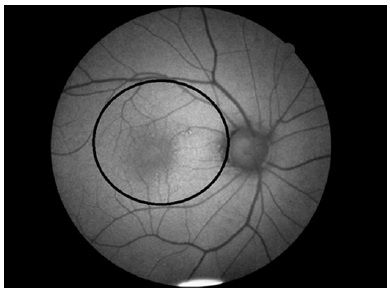

CFI and FAF imaging were performed with a CX-1 digital mydriatic retinal camera (Canon Inc., Tokyo, Japan). Pupillary dilation was performed with 1% tropicamide in all cases before imaging. After CFI, FAF imaging was performed in FAF mode (exciter filter, 530-580 nm; barrier filter, 640 nm; field, 30°) in the same room under standard environmental light. A single FAF image was recorded at high quality for each patient. In the acquired FAF images, 5.5 mm diameter area between the superior and inferior temporal vascular arcuates, as the macula, and an area of 1.5 mm in diameter in the center of the macula, as the fovea, were manually marked by two experienced ophthalmologists (Figure 1). After marking the macula and fovea, all images were recorded as 512x512-pixel, 16-bit, grayscale, tagged image file format, and analyzed with MATLAB 2013a software (MathWorks, Inc., Natick, MA, USA) and the average pixel intensity (API) and average curve width (ACW) of the macula and fovea were measured.

13-fig01.jpg)